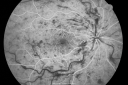

49-year-old woman has central retinal vein occlusion right eye with fluctuating vision and then recently her vision declined and she developed macular edema. I was worried about her angle and you were kind enough to do a peripheral iridotomy and I am dilating her today. Her vision is still poor. VISUAL ACUITY: OD 20/100. IOP: OD 20. There is a peripheral iridotomy, lens is clear, there is no rubeosis. EXTENDED OPHTHALMOSCOPY: OD: Vertical C/D ratio is 0.1. There is 2+ optic nerve edema, 3+ cystoid macular edema. The retinal veins are dilated in all 4 quadrants. The photos confirm clinical findings. Fluorescein angiogram shows some substantial delay in the venous circulation time with no non-profusion. IMPRESSION: 1. PERFUSED CENTRAL RETINAL VEIN OCCLUSION RIGHT EYE. 2. MACULAR EDEMA IN THE RIGHT EYE. DISCUSSION: I explained to the patient that with intravitreal Kenalog there is about an 80% chance of drying up the macula and improving the vision. There is a risk of cataract and glaucoma and a very low risk of infection. I injected the eye today without difficulty with the Kenalog.